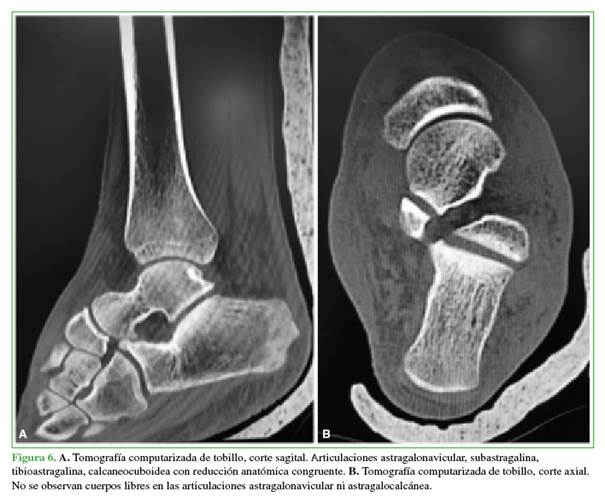

El paciente permaneció en observación por 24 h para tratar el dolor y tomar una tomografía computarizada con el fin de evaluar adecuadamente una reducción congruente, descartar fracturas asociadas, cuerpos libres o lesiones no diagnosticadas antes. Los estudios por imágenes de control mostraron la corrección de la luxación sin fracturas en el astrágalo ni fracturas ocultas (Figura 6).

Las fortalezas de nuestra presentación son el diagnóstico precoz con solo un par de radiografías adecuadamente tomadas cuando el paciente ingresó en el Servicio de Urgencia, una reducción bajo anestesia general de manera atraumática, la inmovilización apropiada con restricción del apoyo y el control posoperatorio con estudios por imágenes que corroboraron haber alcanzado el objetivo: una reducción “biarticular” congruente sin fracturas iatrogénicas ni cuerpos libres intrarticulares.